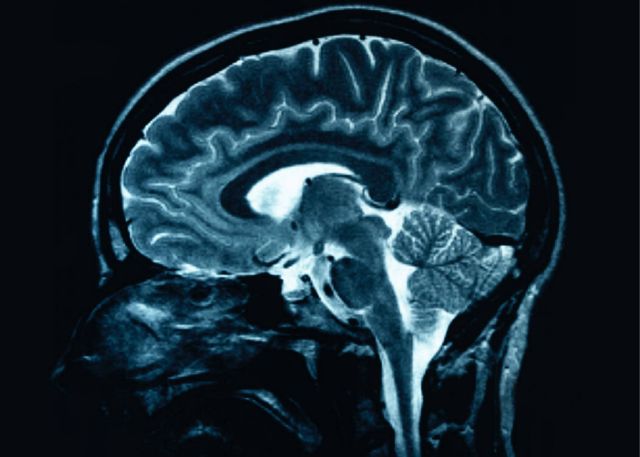

Γερμανοί επιστήμονες έκαναν ένα ακόμα βήμα στην προσπάθεια να αναπτυχθεί ένα τεστ αίματος που θα μπορεί να διαγνώσει έγκαιρα τη νόσο Αλτσχάιμερ. Σήμερα δεν υπάρχει μια αξιόπιστη βιολογική διαγνωστική μέθοδος και οι γιατροί συνήθως αρκούνται σε απεικονίσεις του εγκεφάλου, νοητικά-μνημονικά τεστ και γενικότερη αξιολόγηση των συμπτωμάτων του ασθενούς.